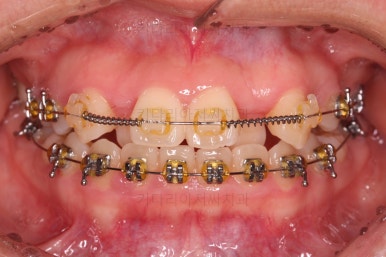

우선 장치를 저희 키다리아저씨치과에서 사용하는 장치로 바꿔 부착을 했어요.

세라믹에서 메탈로 안좋아진 것 아닌가요?

왼쪽이 처음 내원하셨을 당시의 입안 모습이고요. 오른쪽이 장치를 바꿔 부착한 이 후의 모습이에요.

세라믹에서 메탈로 다운그레이드 된 것처럼 보이죠?

사실은 훨씬 좋아진 장치랍니다.

유심히 보시면 왼쪽은 철사를 장치와 연결시키기 위해서 노란색 고무줄로 일일이 묶어줘야 하는 타입인데 비해, 오른쪽은 철사를 묶는 고무줄이 안보이죠?

바로 "자가결찰장치"라고 해서 브라켓에 일일이 뚜껑이 달려 있어서 철사를 장치 스스로가 직접 잡아주는 타입이에요.

그래서 메탈이라고 다 예전장치가 아니라는거죠.

메탈이라고 모두 예전 장치가 아니고 세라믹이라고 모두 최신 장치가 아닙니다.

자가결찰이 예전 장치에 비해 장점이 훨씬 많아서 아무리 세라믹이라고 한들 자가결찰 메탈이 훨씬 좋은 장치에요.

자가결찰 중에서도 재료가 메탈이 있고, 세라믹도 있어요.

(자가결찰 메탈, 자가결찰 세라믹 등)